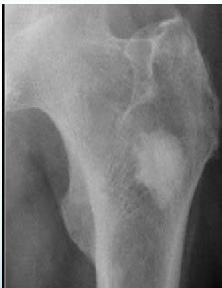

X-rays

- Which bone, and which site in bone?

- Solitary or multiple?

- Bone forming or bone eating?

- Margins: well-defined or ill-defined?

- Calcifications in the lesion?

- Is cortex eroded or destroyed?

- Is there periosteal new bone formation?

- Soft tissue extension?